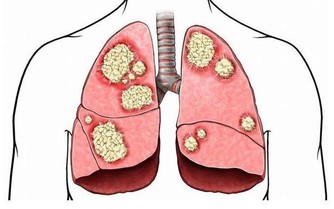

毒素不清,會累積成癌

在大腸癌的發生部位和發生機率中,

直腸和乙狀結腸得癌症的機率最高,

幾乎有百分之七十的腸癌

都集中從肛門上來六十公分的這一段,

因為這裡是宿便最容易囤積的地方,毒素都累積在這裡,

這段腸子就像家裡的垃圾桶,等到垃圾積滿了才會去倒。

咖啡灌腸最主要就是針對這一段腸道進行清腸排毒。

腸癌目前高居國人癌症發生人數的第一名,

是有跡可循的,證明現代人飲食中的毒素真的太嚴重,

加上排泄不良,宿便的毒素都累積在大腸內。

腸癌真的很可怕啊!

往往有症狀出現時,已經是末期了!

除了排便要規律,也要適時去做個身體檢查較保險喔~